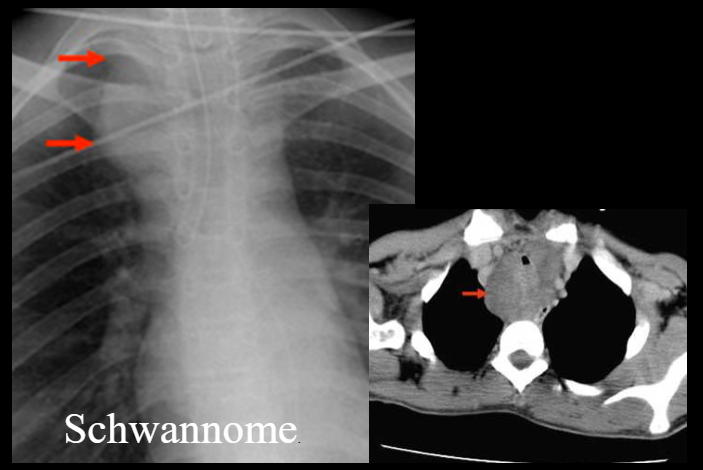

Signe cervico-thoracique

- Opacité médiastinale supérieure Visible au dessus de la clavicule

- Est obligatoirement postérieure